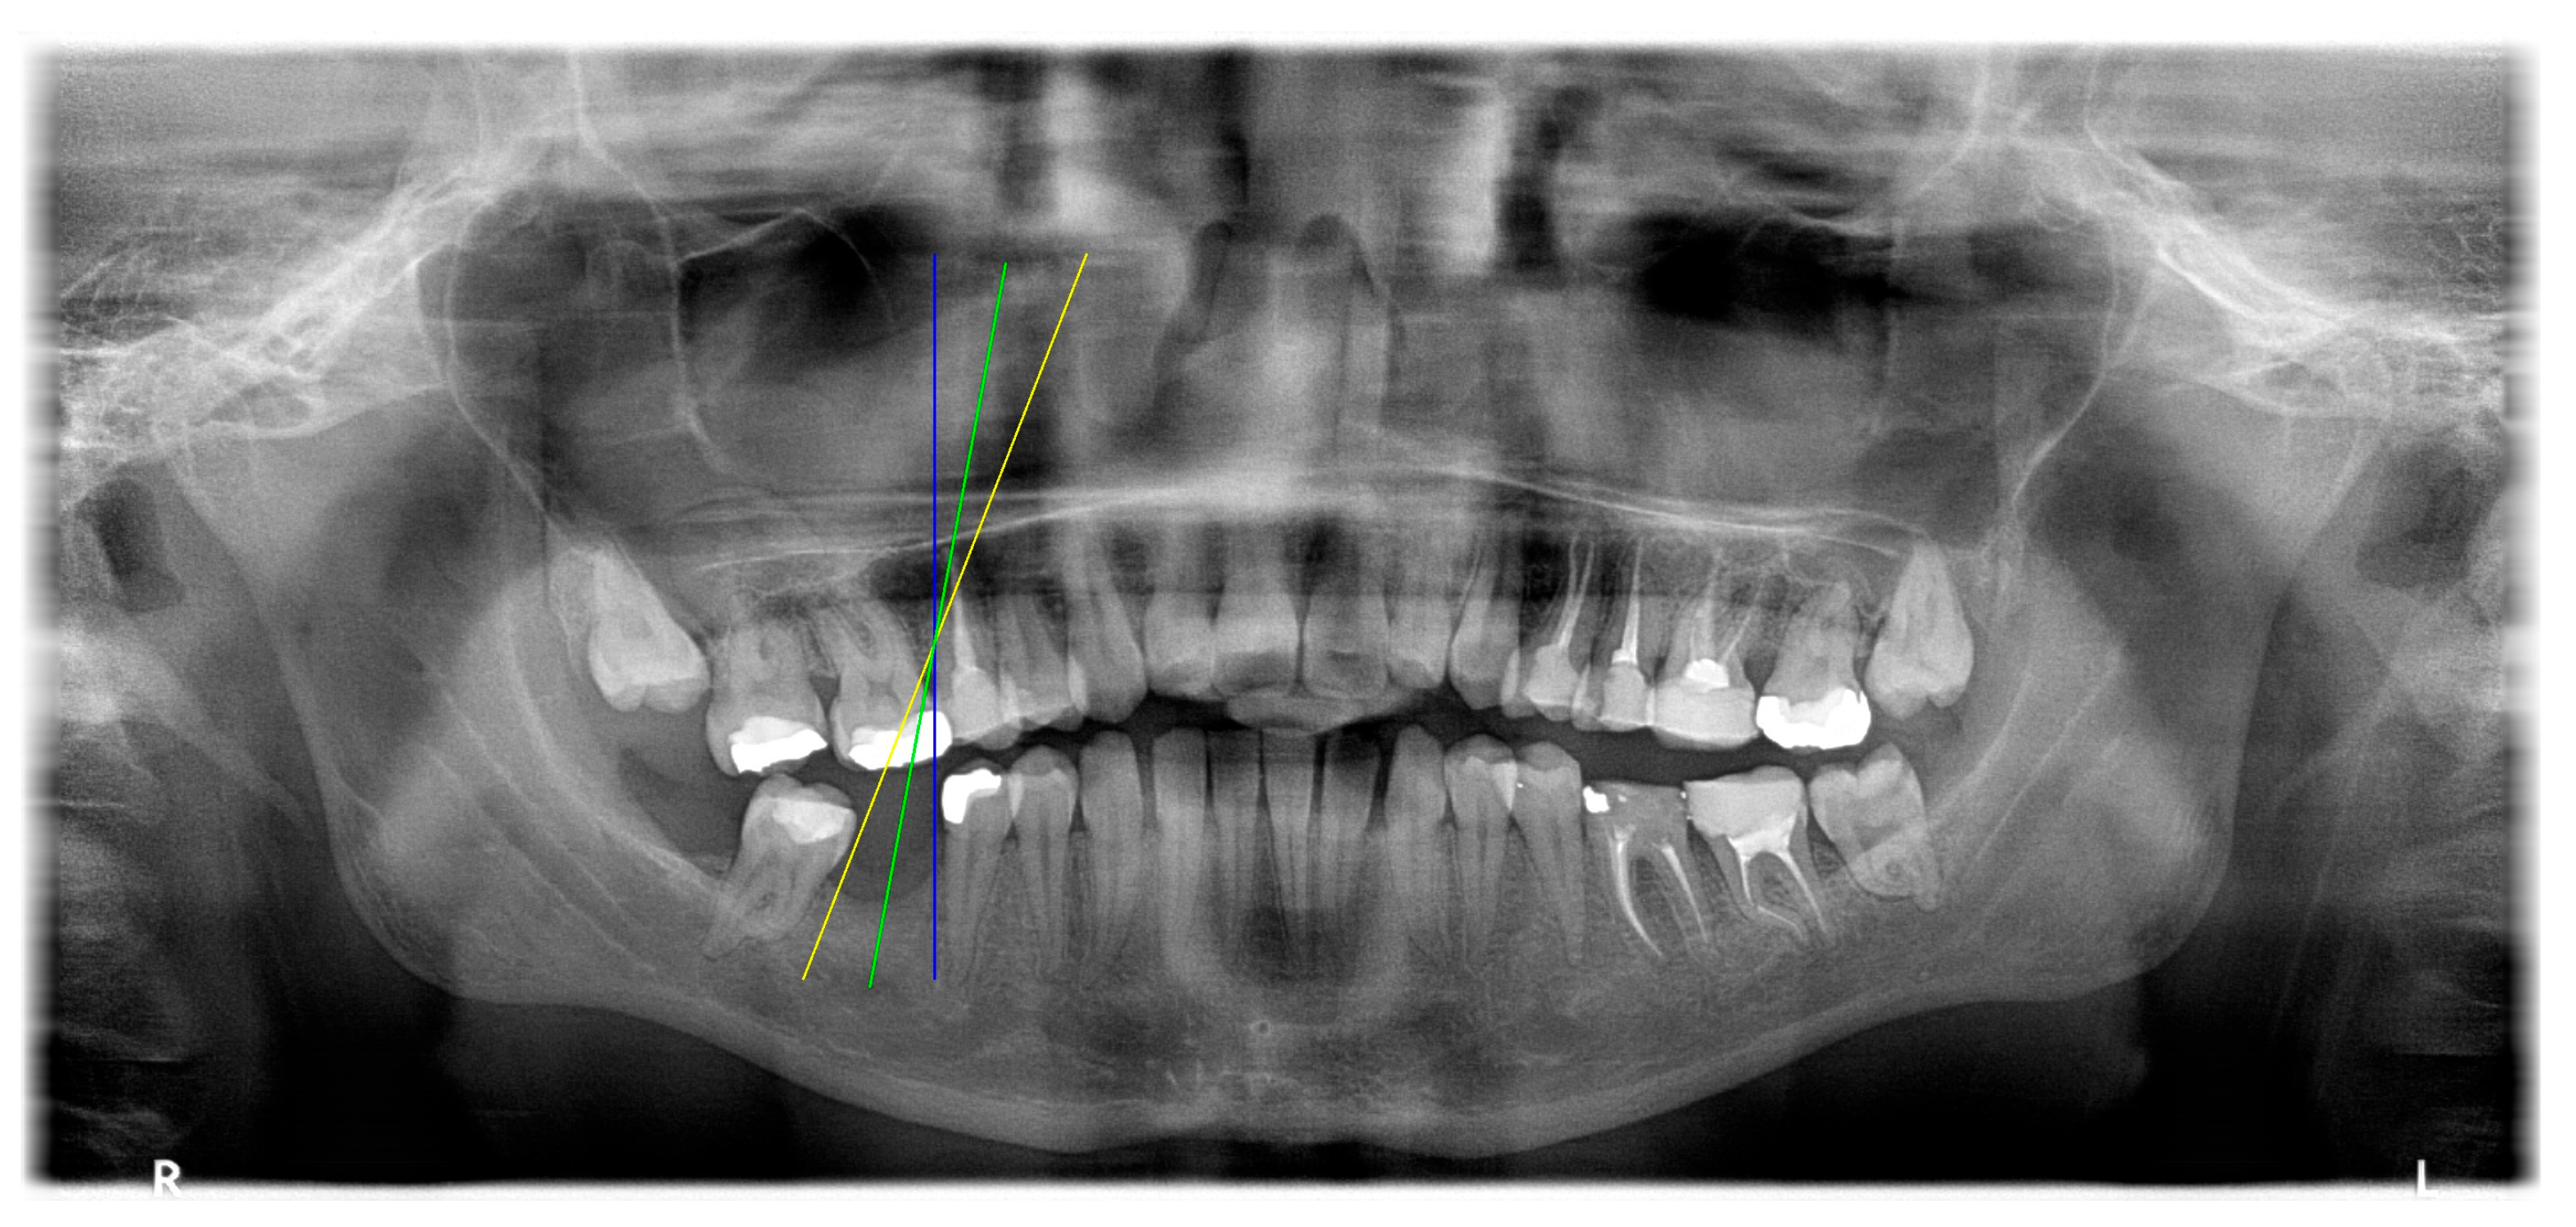

2.4. Implant Pathway Orientation Visualization Algorithm

3.3. Comparison with Clinical Ground Truth and AI-Assisted Framework

| YOLO-OBB result | ||||||

| Validation Image 1–6 | ![]() | ![]() | ![]() | ![]() | ![]() | ![]() |

| Accuracy | 84.13% 75.18% | 90.29% 76.49% | 87.38% 87.27% | 80.40% 84.48% | 70.11% 83.41% | 88.46% 76.33% |

| AI-assisted and implant path visualization result | ||||||

| Comparison with dentist’s ground truth (black line) and our framework (green line) | ||||||

| MSE | 3.59 | 1.29 | 0.41 | 0.80 | ||